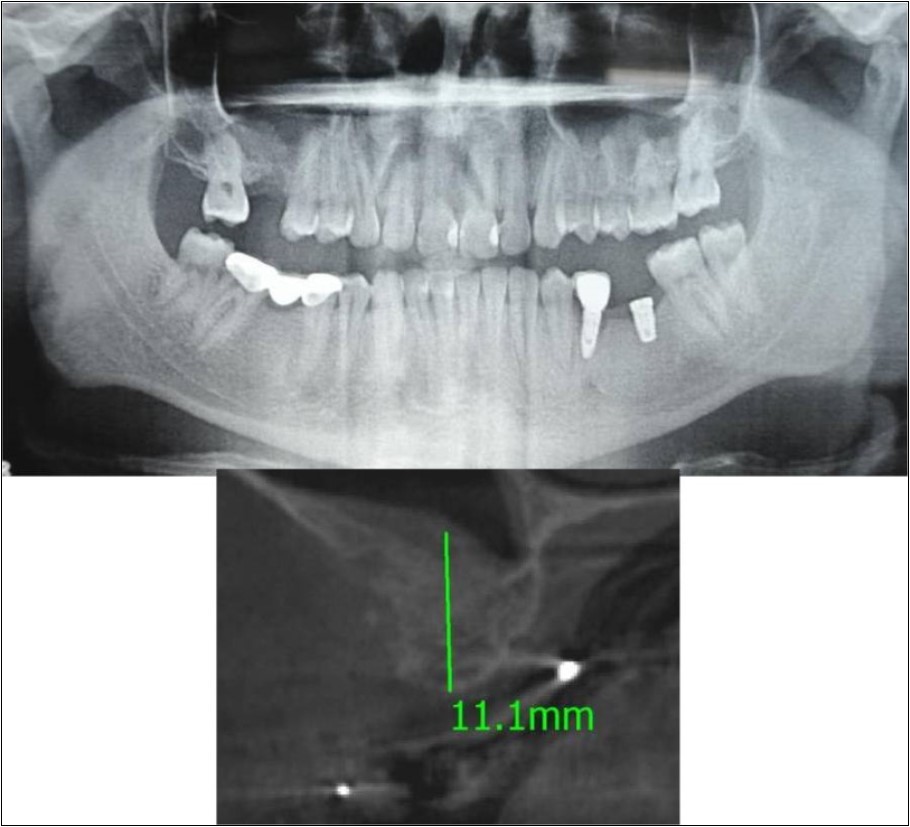

Case Report 4:

A 19 years old young female patient reported to the Department of Oral and Maxillofacial Surgery, D.A.P.M.R.V Dental College and Hospital seeking options for replacement of her missing right and left upper first molars with a fixed prosthesis as she was uncomfortable with the removable partial denture i.r.t 16 and 26. The teeth were extracted 6 months ago because of gross loss of crown structure and poor prognosis for root canal treatment. Patient was also undergoing fixed orthodontic treatment for proclined upper anteriors. Patient did not give history of any existing sinus pathologies. All possible rehabilitative options were explained to the patient and a treatment plan of replacement of missing teeth with implant supported prosthesis using two dental implants was finalized.

Clinical and Radiological Assessment:

1.Partially edentulous maxillary arch with missing 16 and 26;

2.Increased pneumatisation of right and left maxillary sinus;

3.Height of available bone-

16 region: 6.5mm;

26 region: 6.2mm;

4.Transverse thickness of available bone (CBCT evaluation)-

16 region: 8.3mm;

26 region: 10.5mm;

5.Fixed orthodontic appliance;

6.Inter-ridge space adequate to place implant (11mm).

Treatment:

Patient underwent the procedure of indirect sinus elevation using sinus osteotomes in relation to 26 region. Calcium phosphosilicate putty was dispensed as the graft material through the crestal osteotomy site to maintain the elevated sinus membrane followed by placement of 5 x 10mm dental implant under local anaesthesia and strict aseptic protocols. The implant was allowed to osseo-integrate for a period of six months during which the patient was followed-up periodically and was assessed for peri-implantitis, crestal bone loss and mobility. Patient was taken-up for direct sinus elevation via lateral window approach for sinus augmentation i.r.t 16 region. Under aseptic conditions and local anaesthesia, lateral wall of maxilla was exposed after muco-periosteal flap elevation. A window was created of 1cm diameter corresponding to apical aspect of 16. Sinus membrane was identified and elevated using sinus elevators and reamers without perforating the lining. Once the sinus membrane was elevated, phosphosilicate putty was dispensed through the lateral osteotomy site as the graft material to achieve an augmentation of 1cm assessed clinically and confirmed using post-operative OPG. At the end of 6 months, a repeat CBCT scan was advised to evaluate the increase in bone height. (Figure 13a,b, pre-treatment; Figure 14a,b, post-treatment)

Figure 13.(a,b) Pre-treatment OPG and cross section of CBCT showing residual alveolar bone height for Case No.4;

Figure 14.(a,b) Post-treatment OPG and cross section of CBCT showing residual alveolar bone height for Case No.4;